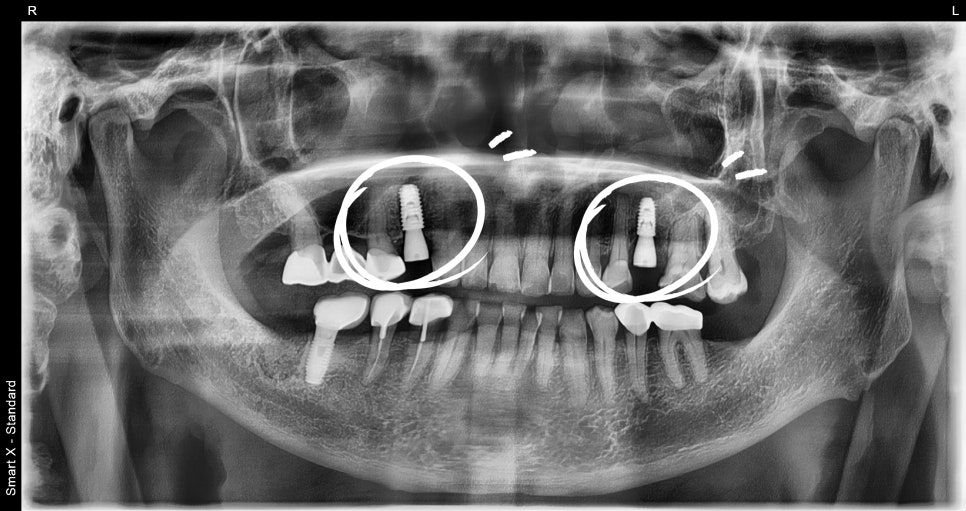

② Placement of 2 insurance-covered implants

– Under local anesthesia, two implants were placed in the mandibular molar area.

– The surgery took about 20 minutes, and it is a method that can be performed without significant burden even for elderly patients.

③ Waiting for implant osseointegration (about 2–3 months)

– During the osseointegration period, when the bone and implant firmly bond,

we combined soft meals with oral hygiene management.